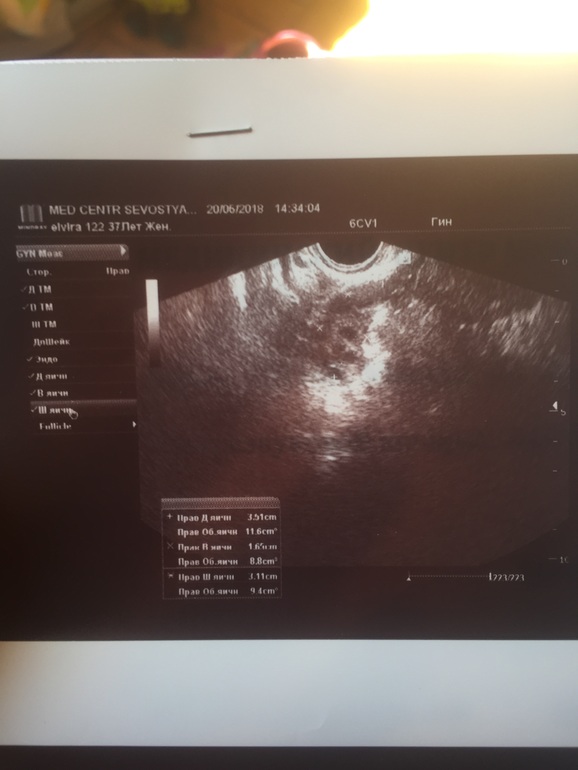

Здравствуйте,вчера была на УЗИ,болит то справа то слево в области яичников отдаёт иногда в ногу и спину.

Врач УЗИ говорит все чисто матка хорошая,шейка и придатки хорошие чистые.

Есть свободная жидкость в малом количестве,спросила значит прошла овуляция,она говорит наверное...

После говорит что не видит доминантного фолликула и вообще говорит что яичники похожи на поликизтозные,хотя я у прошлом месяце была на УЗИ все было хорошо и фолликул был и жёлтое тело помогите разобраться фот снимки УЗИ